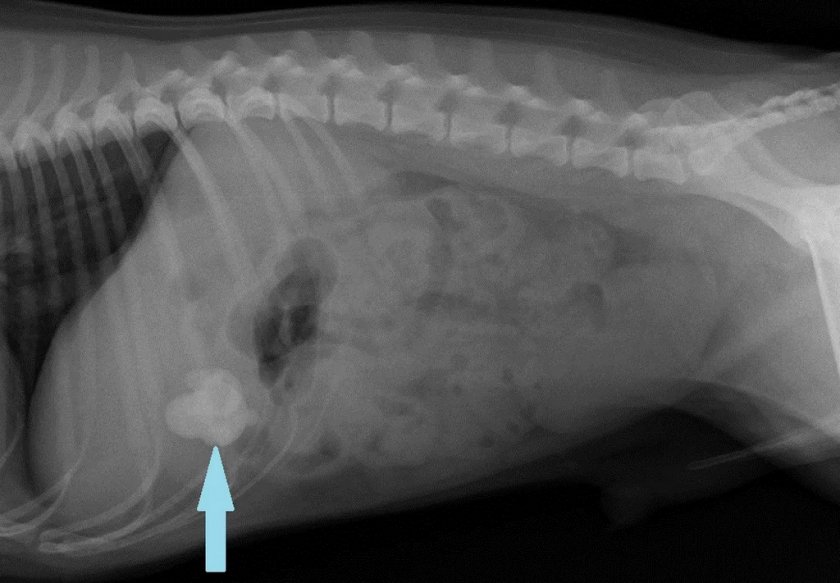

Диагностика проблемы — всегда первый этап на пути к успешному излечению заболевания. При подозрении на закупорку кишечника врач проведёт полный осмотр пациента, расспросит владельца об особенностях его поведения и рационе питания в последнее время, а также назначит ряд дополнительных диагностических процедур. Помимо привычного анализа мочи и крови, собаке предстоит пройти УЗИ, а при возможности клиники ещё и рентгенографическое исследование в прямой и боковой проекции с применением контрастного красящего вещества. В сравнении со стандартным УЗИ, этот метод отличается более высокой информативностью, а из минусов выделяют необходимость использования наркоза во время процедуры.